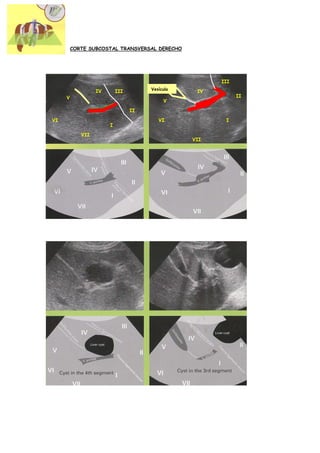

CORTE SUBCOSTAL TRANSVERSAL DERECHO

III

Vesícula

IV       III                    IV

V                                                       II

V

II

VI                                       VI             I

I

VII

CORTE SUBCOSTAL TRANSVERSALDERECHO III Vesícula IV III IV V II V II VI VI I I VII VII